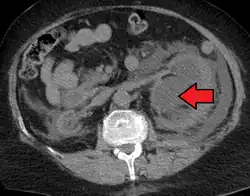

CT scan of bilateral hydronephrosis due to a bladder cancer

CT scan of bilateral hydronephrosis due to a bladder cancer -

Massive hydronephrosis as marked by the arrow

Massive hydronephrosis as marked by the arrow -